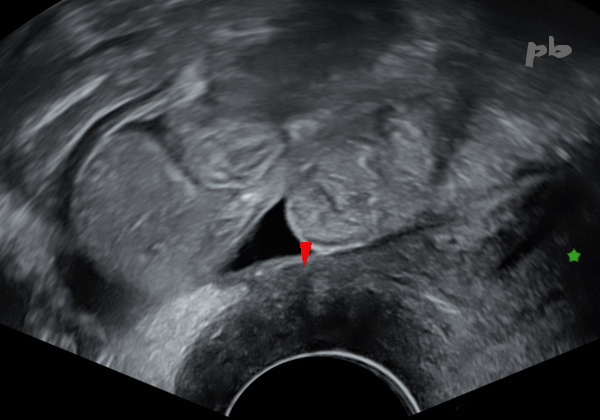

19bis – Endométriose digestive

Echographie endovaginale coupe sagittale (à gauche) – IRM coupe sagittale T2 (à droite).

Volumineux nodule endométriosique situé sur le torus (►) et infiltrant en arrière la paroi antérieure du rectosigmoïde.

Cette envahissement (entre les croix – ★) apparait plutôt hypoéchogène et hyposignal. La lumière digestive est respectée en IRM. Interruption de la musculeuse (►) en regard du nodule en échographie.

Utérus (♦)

Cette endométriose profonde n’a été découverte qu’en cours de stimulation ovarienne, alors que les douleurs remontaient à plusieurs années en arrière : ce qui montre la difficulté du diagnostic, et probablement le développement des lésions sous stimulation.